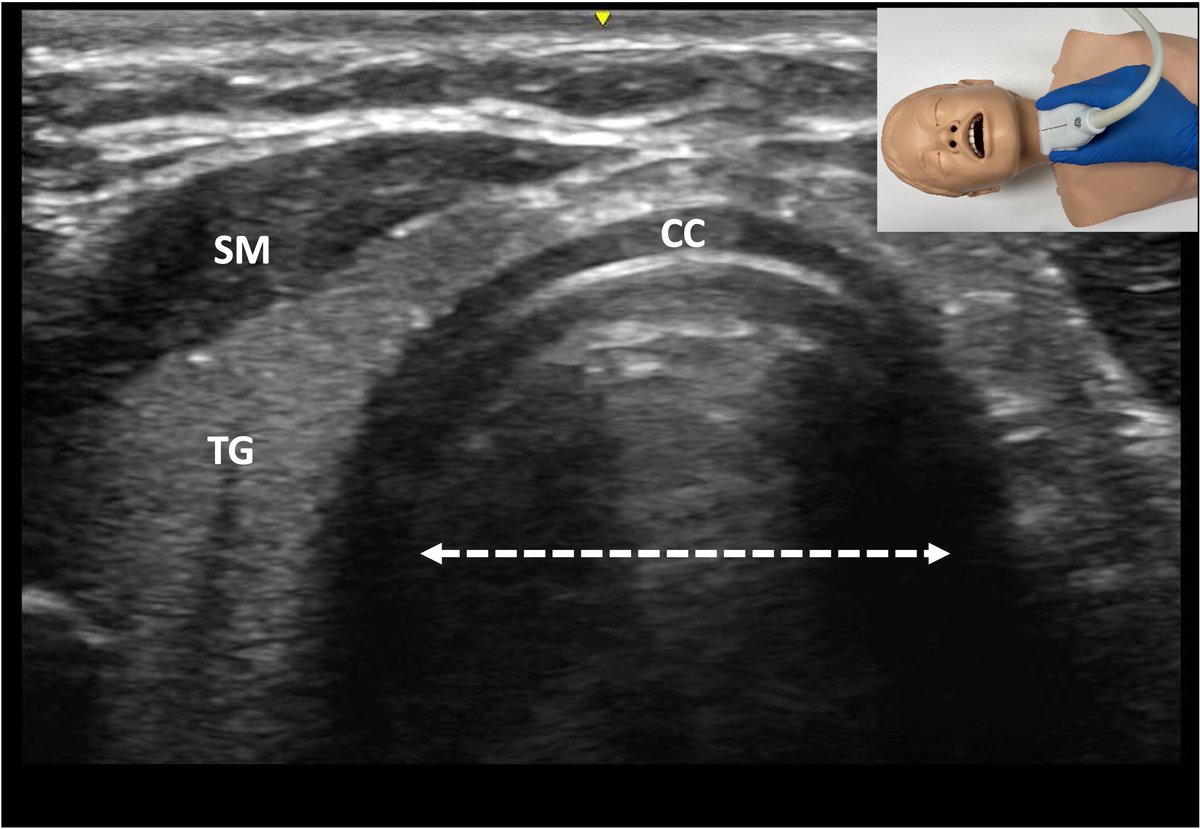

Our recent scoping review of Ultrasonographic Techniques in the Evaluation of the Pediatric Airway. Congrats to Dr. Burton for his excellent work on the paper. onlinelibrary.wiley.com/doi/10.1002/ju…

Our recent scoping review of Ultrasonographic Techniques in the Evaluation of the Pediatric Airway. Congrats to Dr. Burton for his excellent work on the paper.